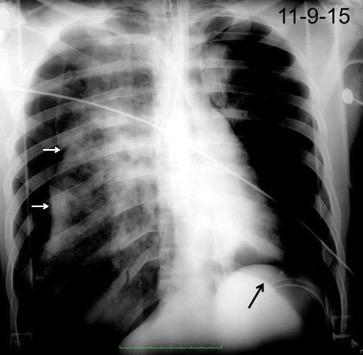

Marzo 2014: Perforación longitudinal distal secundaria a episodio de vómito (síndrome de Boerhaave). Derrame pleural izdo. que evoluciona a empiema.

Wang C-T et al. Tension hydropneumothorax in a Boerhaave syndrome patient: A case report . World J Emerg Med, 2021. Katabathina V et al. Nonvascular, nontraumatic mediastinal emergencies in adults:a comprehensive review of imaging findings. Radiographics. 2011.